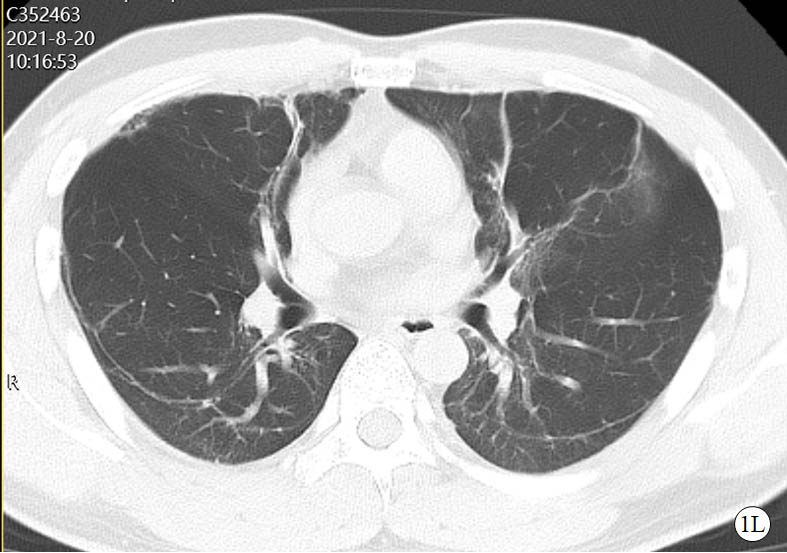

图 1 患者口服百草枯后胸部CT影像学变化

2021-08-20 CT图